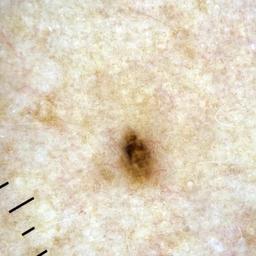

ISIC_4902807

710 x 710

Clinical

Field Value

acquisition_day 207

age_approx 45

anatom_site_1 Upper extremity

anatom_site_general upper extremity

diagnosis_1 Benign

diagnosis_confirm_type single image expert consensus

fitzpatrick_skin_type I

image_type dermoscopic

personal_hx_mm True

sex female